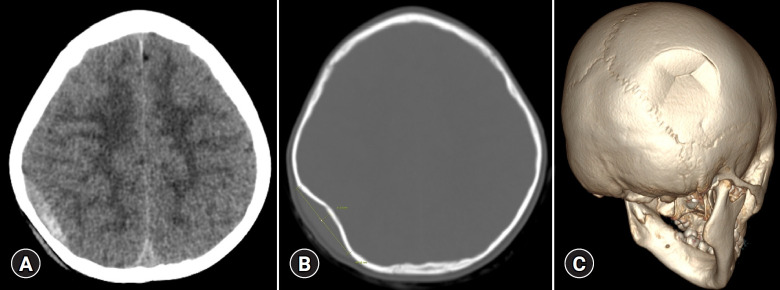

A 5-year-old female pediatric patient with head trauma was transferred to our regional trauma center. A depressed skull fracture measuring 45 mm in diameter and 6 mm in depth was diagnosed using a 3-dimensional (3D) computed tomography (CT) scan. Despite the absence of significant neurological symptoms, the extent of the depression necessitated surgical intervention on the third day of hospitalization. Using a 2 mm micro burr, two holes were drilled at strategically selected points of the fracture identified by 3D CT. Adson blunt dissecting hooks were inserted through the burr holes to elevate and reduce the fracture. Postoperative CT scans, including a follow-up scan on the 36th day, demonstrated stable reduction. The minimally invasive technique applied for pediatric depressed skull fracture reduction may significantly reduce pain, shorten recovery time, and decrease hospitalization duration, yielding favorable outcomes.